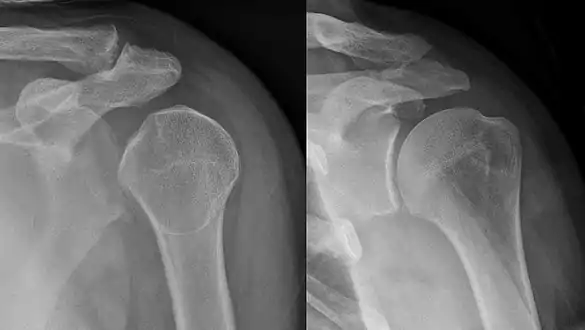

• Dislocated shoulder

• Shoulder dislocations account for 45% of all dislocation visits to the emergency room.[24] Anterior shoulder dislocation, the most common type of shoulder dislocation (96-98% of the time) occurs when the arm is in external rotation and abduction (away from the body) produces a force that displaces the humeral head anteriorly and downwardly.[24] Vessel and nerve injuries during a shoulder dislocation is rare, but can cause many impairments and requires a longer recovery process.[24] There is a 39% average rate of recurrence of anterior shoulder dislocation, with age, sex, hyperlaxity and greater tuberosity fractures being the key risk factors.[25]